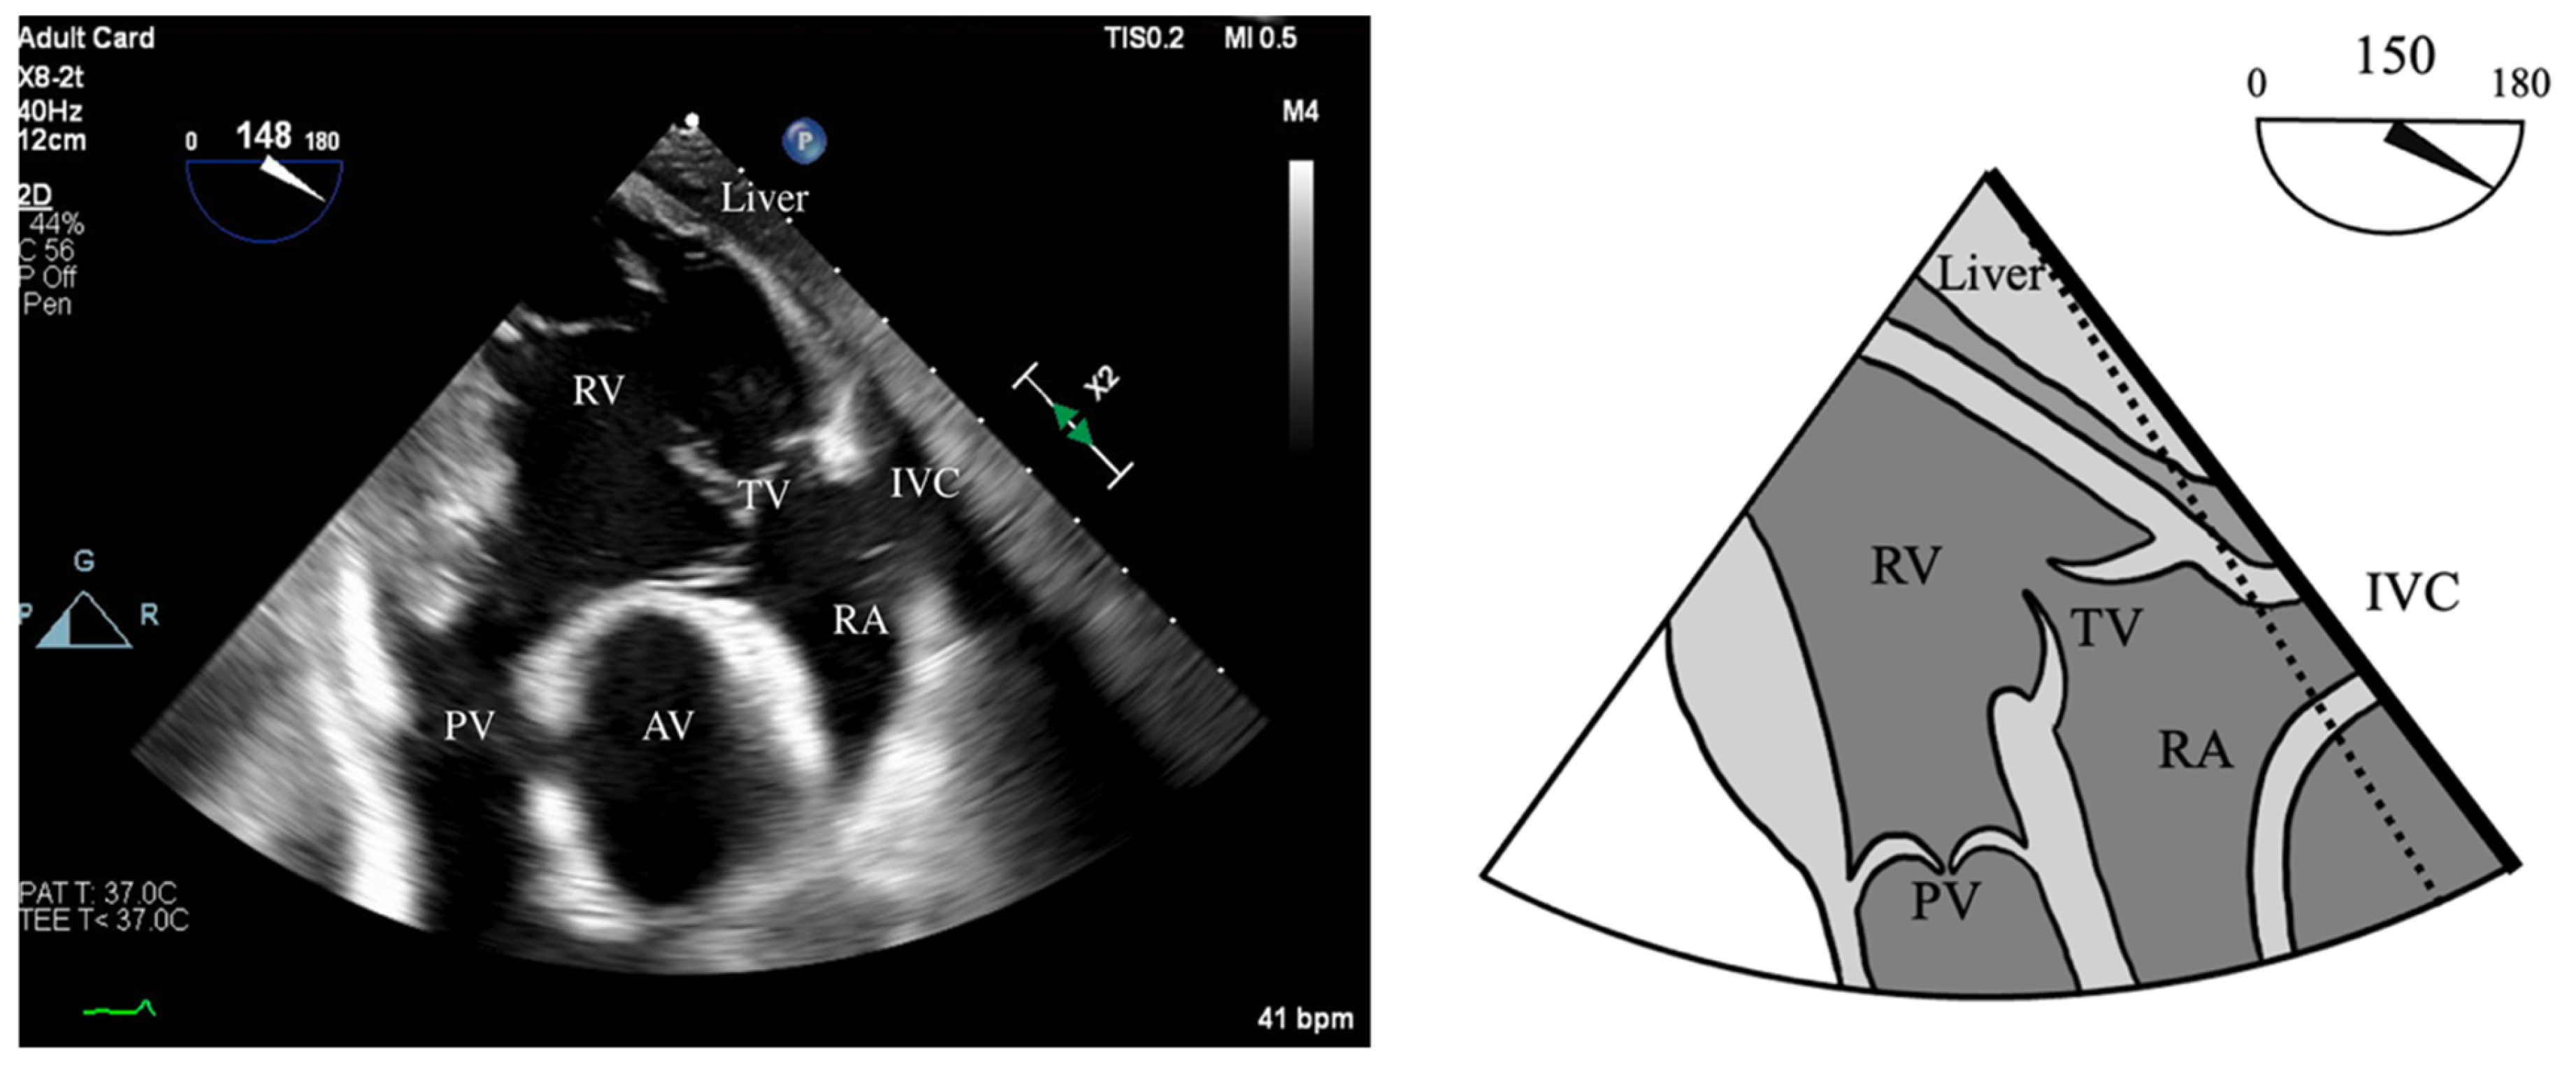

- RV Fractional Area Change (FAC): Measured in the ME-4C view, normal >35%.

- Tricuspid Annular Plane Systolic Excursion (TAPSE): ME-RV Inflow/Outflow with angle correction over lateral tricuspid annulus, normal >1.6 cm/s.

- S’: Measured from a non-standard TEE view. In the Deep Transgastric long axis (DTG-LAX) view, omniplane to 120–150° and turn right. The RV and lateral tricuspid annulus will be centered on the screen. Tissue Doppler Imaging (TDI) is then used to measure the systolic velocity of the lateral tricuspid valve annulus (S’) with >10 cm/s considered normal [79] (Figure 4 and Figure 5).